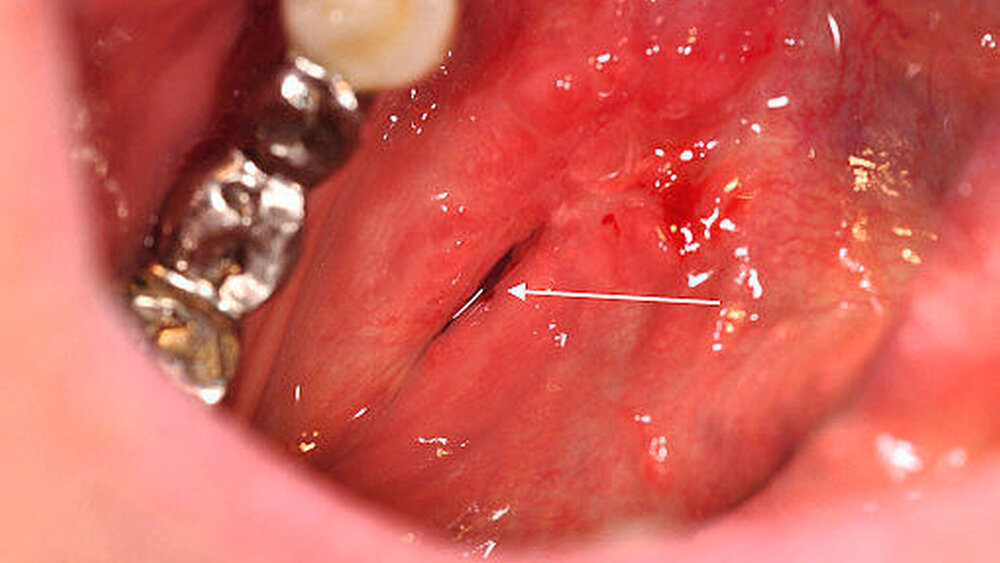

Die Antikoagulation wurde unverändert weitergeführt, wobei der Eingriff am Morgen vor der Einnahme der nächsten Tablette stattfand. Nach Schienung des Warthon-Gangs via Kunststoffröhrchen zur Identifikation desselben erfolgten die Eröffnung des Ganges sowie die Darstellung und Bergung des Speichelsteins (Abbildungen 4 und 5) bei einer Größe von 2 cm x 1,3 cm. Das intraoperativ geborgene Konkrement (Abbildung 6) konnte eindeutig als Speichelstein (Sialolith) identifiziert werden. Eine weiterführende histopathologische Dignitätsklärung war nicht erforderlich. Der eröffnete Ausführungsgang wurde über nicht resorbierbare Nähte im Sinne einer Marsupialisation an den Mundboden angesteppt und so die neue Mündung nach proximal verlegt.

Unter Einhaltung der empfohlenen Verhaltensregeln – wie dem anfänglichen Meiden von fester und heißer Nahrung – verlief die Wundheilung zeitgerecht und komplikationslos. Bei der abschließenden Nachuntersuchung zwei Wochen nach dem operativen Eingriff war die Patientin bei intraoral reizfreien Verhältnissen vollkommen beschwerdefrei (Abbildung 7). Aus der proximalen Mündung des Wharton-Gangs ließ sich schmerzfrei Speichel exprimieren. Der Nervus lingualis war zu keiner Zeit beeinträchtigt.